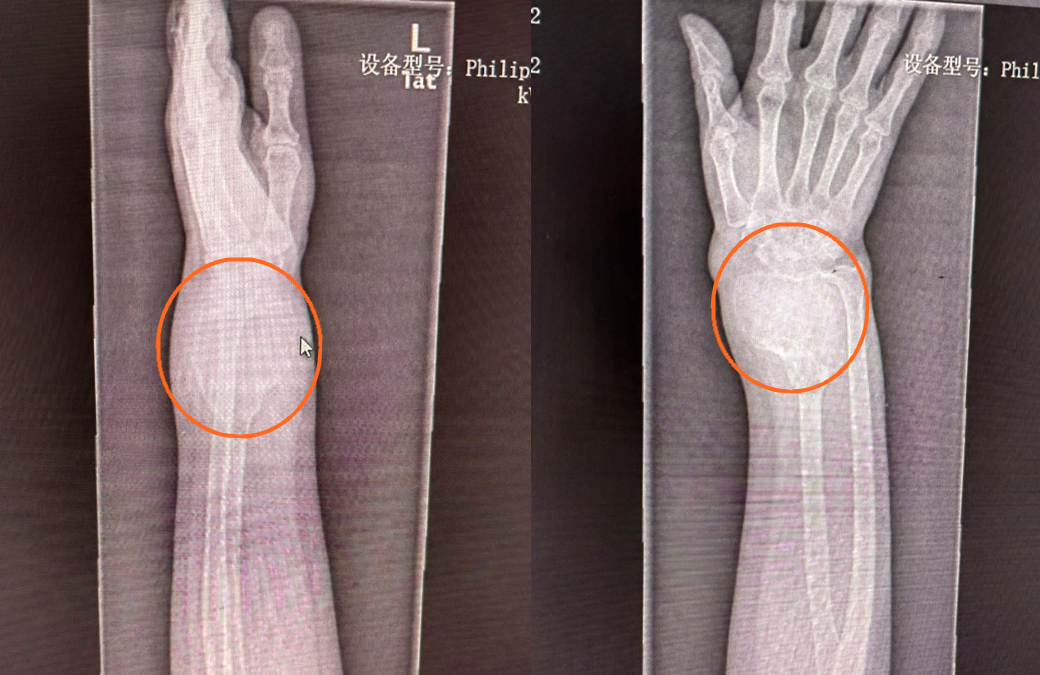

51歲的患者稅女士,一年前左前臂遠(yuǎn)端不明原因的出現(xiàn)一個(gè)包塊,她以為就是個(gè)軟組織包塊,沒太當(dāng)回事,包塊越來越大,到醫(yī)院拍片子一看,整個(gè)橈骨下段長(zhǎng)達(dá)十多公分的骨頭上長(zhǎng)的包塊已經(jīng)像個(gè)氣球一樣?!斑@個(gè)包塊是骨巨細(xì)胞瘤,是原發(fā)性骨腫瘤,長(zhǎng)這么大,還是比較少見的,雖然是骨的良性病變,具有較強(qiáng)的侵襲性和轉(zhuǎn)移能力,會(huì)對(duì)骨質(zhì)有明顯的破壞性,需要進(jìn)行手術(shù)治療。”官常和醫(yī)生看了片子跟患者交流。